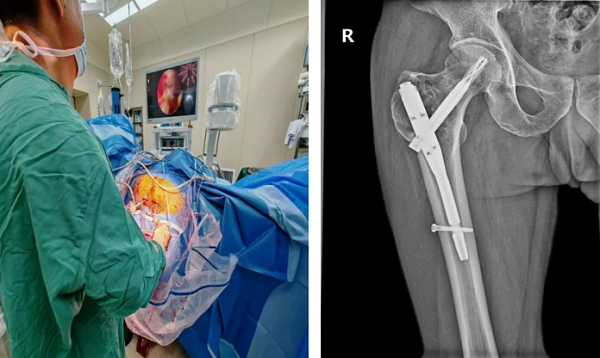

近日,玉溪市人民医院骨外二科专家团队迎来技术突破——成功完成全市首例关节镜辅助下股骨近端骨巨细胞瘤切除术,并同步实施自体髂骨+人工骨植骨术、股骨近端内固定术。该手术不仅为54岁患者杜先生驱散病痛,更填补了玉溪地区关节镜技术应用于良性骨肿瘤治疗的空白,为同类复杂病例提供了新的治疗范式。

手术在全麻下开展,团队创新性采用关节镜辅助技术——通过关节镜的360°无死角视野,精准定位肿瘤病灶,借助专用器械彻底清除肿瘤组织;针对肿瘤较大导致的骨缺损,术中植入自体髂骨与人工骨混合骨材,并进行股骨近端内固定以恢复骨骼稳定性。

与传统手术相比,此次手术全程在关节镜监视下操作,不仅创伤更小,清晰观察瘤腔情况,还能通过低温等离子技术对残留肿瘤细胞进行灭活,有效降低复发风险,同时最大程度保护周围健康组织。

术后恢复效果超出预期:杜先生在术后第二天即可下床拄拐进行患肢不负重行走训练;术后1个月复查时,其髋部疼痛完全缓解,已能实现完全负重行走,影像学检查显示肿瘤病灶无扩大迹象,骨骼愈合情况良好。